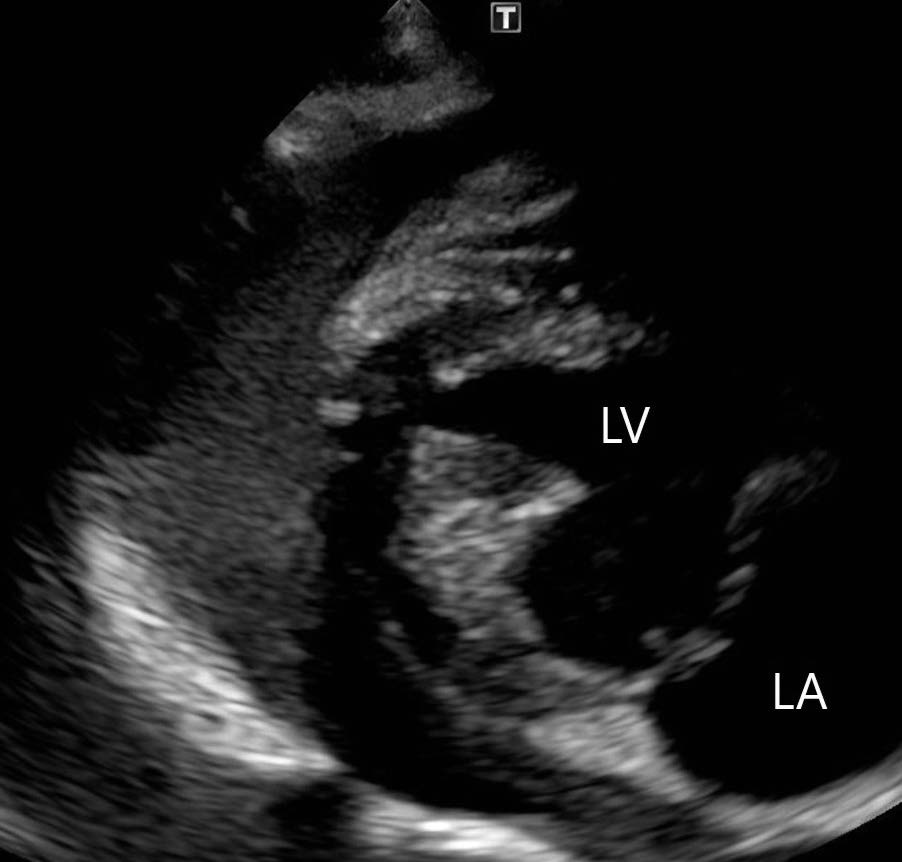

ポイント・オブ・ケア胸部超音波検査:図1 及び2

図1 左側胸壁の肺エコー画像

図1 は症例の左側胸壁からの肺エコー像で,正常な肺で観察されるA ラインを示している.正常であれば高エコー性に描出される肺胸膜ラインの下方に多重反射により形成されたA ラインが認められる.肺水腫であった場合には肺胸膜ラインから垂直方向に減衰せずにA ラインをかき消す高輝度線状アーチファクトであるB ラインが観察されることがある.本症例では両側いずれの領域においてもBラインが認められなかったことや経皮的動脈酸素飽和度が正常であったことから,急性心不全による肺水腫は否定的と判断した.図2 は心膜液貯留と心膜腔内の血餅を疑う構造物を示している.心外膜の外側(心膜腔)に無エコー性の液体貯留が認められることから心膜液貯留と判断できる.さらに一部に血餅を疑うエコー源性のある構造物が存在することから左心房破裂による心膜液貯留と診断することができる.本症例はこれまで心不全に起因していると考えられる症状(頻呼吸,呼吸困難など)を呈しておらず,胸部X 線検査と心臓超音波検査で心拡大の基準(EPIC 基準)を満たしていたことからMMVDACVIM stage B2 と診断された.左心房破裂は心不全を呈したことのないstage B2 でも認められることがある(15 頭中6 頭がstage B2)と報告されているため,心不全の既往がなかったとしても除外できない点に注意する必要がある[1].